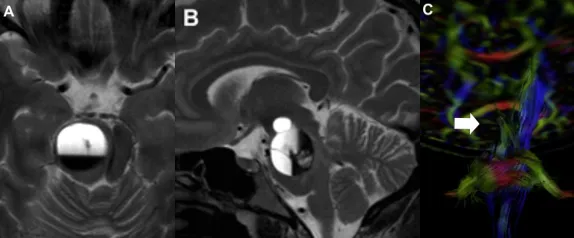

这台手术由巴特朗菲教授主刀。虽然病灶周围紧邻面听神经、三...